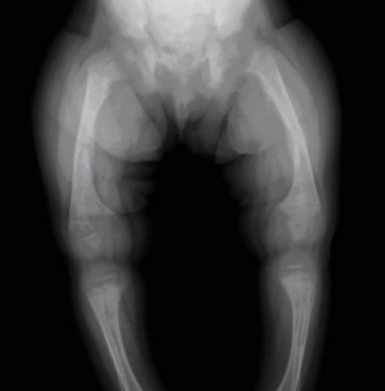

METHODS: Concentrations of serum 25(OH)D, calcium, phosphorus and alkaline phosphatase were measured in normal control (n=73), suspected rickets (n=45) and confirmed rickets groups (n=65). Receiver operating characteristic (ROC) curve was used to evaluate the diagnostic value of serum 25(OH)D for rickets.

RESULTS: Serum 25(OH)D levels in the suspected and confirmed rickets groups were 83±30 and 72±31 nmol/L respectively, which was lower than in the normal control group (112±37 nmol/L) (P<0.01). There was no significant difference between the suspected and confirmed rickets groups (P>0.05). Vitamin D deficiency rates in the suspected and confirmed rickets groups were higher than in the control group (P<0.01). The ROC curve area of serum 25(OH)D for the diagnosis of rickets was 0.760 (95%CI 0.692-0.820, P<0.01), and the optimal operating point was 90.70 nmol/L (sensitivity 68.49%, specificity 72.73%). There was no significant difference in levels of calcium, phosphorus and alkaline phosphatase between the three groups (P>0.05).

CONCLUSIONS: Serum 25(OH)D levels in infants with suspected and confirmed rickets are significantly reduced and this may reflect vitamin D deficiency . Therefore, it may be useful to check serum 25(OH)D levels in screening for rickets.

||Group|nmol|ng

Suspected Rickets|83 nmol| 33ng

Confirmed Rickets|72 nmol|29 ng

Not rickets| 112 nmol|45 ng

Optimal operating point| 90.7 nmol|36 ng||

( Suspicious group 455 (11) 16 (36) 24 (53) The rickets group of 65 20 (31) 14 (22) 31 (48) X1 33.346 <0.001 Serum 25 (OH) D level was no significant difference between the groups suspicious group and rickets, so the former satisfied rickets group analysis. The area under the curve (AUC) 0 760 (95% C /: 0 692 -0.820,8 <0.001), and the diagnostic accuracy Medium. Calculate the likely cut-off point of sensitivity and specificity, 90.7 nmoZL critical point on the ROC curve, the corresponding sensitivity of 68.49% and a specificity of 72.73%, as shown in Figure 1. o Hi .. ■ ............. ■ ■ ■. 020406080100 1 B {0 / '\ Figure 1 serum 25 (OH) D levels ROC curve 3 Discussion Rickets diagnosis of multiple serum markers as calcium, phosphorus and alkaline phosphatase, but the lack of specificity and sensitivity [7-8], this study also confirmed this point. This may be related to the role of parathyroid hormone and calcitonin, the latter two collaborative vitamin D to maintain the body's calcium and phosphorus balance. 25 (OH) D has the features of high concentration, stability and long half-life, is considered an important indicator to reflect the body's vitamin D metabolism [9], serum 25 (OH) D detection diagnostic value of rickets more and more attention . The this study rickets serum 25 (OH) D level of 72 ± 31 nmollL higher than that of vitamin D deficiency (<50nmol / L) of the diagnostic criteria. Combined with the object of study of medical history, consider primarily related to health care workers and parents of rickets prevention knowledge to understand fully and actively its taking vitamin D supplements related to the baby after birth. Confirmed in the regular, long-term medical environment to add vitamin D, rickets in children with serum 25 (OH) D7 level also increased. Nevertheless, rickets serum 25 (OH) D levels are still significantly lower than the control group, indicating that serum 25 (OH) D levels decreased still prompt the baby may occur rickets a more reliable indicator. ROC curve can be used as a diagnostic method in clinical epidemiology accuracy evaluation index. AUC - like the diagnostic value lower than 0.9 means that a higher diagnostic value between 0.5-0.7. The results of this study serum 25 (OH) D AUC = 0.760, showed that serum 25 (OH) D detection of some diagnostic value. It is noteworthy that the suspicious group and rickets serum 25 (OH) D level was no significant difference, suggesting in typical rickets before, already exists in children, even vitamin D deficiency may be a long time. Further illustrate the serum 25 (OH) D levels decreased for the early detection of rickets significant. At this point, even better than the classic X line. Because the latter can be displayed only when the bone mass loss of 30% to 50% decrease in bone mineral content [W]. Researchers refer to the majority of expert consensus as vitamin D nutritional status evaluation criteria [1115]: serum 25 (OH) D levels <50 nmoZL vitamin D deficiency, 50 -75 nmoZL lack of vitamin D, 75 nmoZL sufficient. 2011, published by the American College of Endocrinology vitamin D deficiency assessment, treatment, and prevention of clinical practice guidelines recommend serum 25 (OH) D levels <50 nmoZL diagnosis of vitamin D deficiency [16]. In fact, no such study in children serum 25 (OH) D the normal uniform standards. Due to the experimental method, latitude, season and vitamin D intake persons and other factors, countries, different children around the serum 25 (OH) D level [17-23]. Which is the limit of the check in the pediatric clinical wider application of one of the factors. Diagnosed rickets in children in this study only 31% (20/65) consistent with vitamin D deficiency, to Diagnosis and treatment of great distress. Therefore, if the application of the above subscript Baby vitamin D nutritional status of prospective evaluation of the area to be combined with the history and clinical performance into account, to avoid missed diagnosis of vitamin D deficiency cases, delaying treatment. ROC curve select the best critical point for a detection means to achieve maximum sensitivity and specificity, while reducing the rate of misdiagnosis and missed diagnosis rate. In this study, 90 7 nmoZL as the diagnostic value of the critical point of view from a sensitivity of 68.49% and 72.73% specificity, there are certain clinical value. Both as soon as possible to prevent and detect the occurrence of rickets, it will not increase the psychological and economic burden of the parents. Due to a limited number of the observed object, needed more time large-scale & randomized, controlled trials testing. Recent Liangguan Yu et al [24] proposed Nanjing 0-10 age group children, serum 25 'OH) D level 50 -60 nmoZL may be the optimal concentration to maintain normal bone metabolism, in addition to still rare in the open literature reports of national laboratories establish its own reference range. In summary, with the prevention of health literacy, domestic severe rickets is rare, early or atypical rickets is more common. Serum 25 (OH) D level of testing for the detection of early rickets and When clinical treatment is even more significant. In view of the more influential factors still exist in the current children's serum 25 (OH) D, under the premise of the normal range has not yet been determined, it is recommended that the serum 25 (OH) D testing as a screening Koh Means of disease hunchback. Lily Chow, Guoqing Mei serum 25-hydroxyvitamin D determination of significance in the prevention of rickets [J]. Eugenics and Heredity, 1996,4 (3) :35-36. Malan, microelement, Tian Yue, Li Jing, Lu Fang, Hou security deposit. infant serum 25-hydroxyvitamin D levels and rickets relationship [J]. Applied Clinical Pediatrics, 2007,22 Diagnostic the Tanghai single photon technology [M] / / honest osteoporosis, Beijing: Science Press, 1998: 59-84. Wu Kangmin vitamin D deficiency rickets [M] / / Liu Xiangyun, Chen Ronghua, Zheng-Yan Zhao child health science. 4th edition. Nanjing: Jiangsu Science and Technology Press, 2011: LI Tong, He Jinsheng vitamin D deficiency rickets [M] / / Hu Yamei, Jiang Fang Zhu Fu Tang Practical Pediatrics (on). 7th edition, Beijing: People's Health Publishing House, 2002 :536-542. Wang Xiaomin, Ma Chao, Fu seedlings. Rickets diagnosis [J; dihydroxyvitamin D3 and bone alkaline phosphatase in the Maternal and Child Health Care of China, 2008, 23 (23): Ma Xiuli, Zhen Yanfen children with asthma serum 25 - Immunoglobulin E changes [J] Chinese Journal of Contemporary Pediatrics, and immune Liang Xiaohong, let Yang, Shu-Ping, Wu Hongyuan children aged .0-2 VD levels of nutrition and related factors [J] Chinese Primary Health Care, 2004, 18 (7): 74-75. Moli Ya Lai original Revising Contributions Chien-Liang Liu, Liu Jianlong infant serum 25-hydroxyvitamin D levels in the diagnosis of rickets [J] Practical Preventive Medicine, 2008, Vitamin D intake of acute lower respiratory tract infection in children [J] Chinese Journal of Contemporary Pediatrics, 2012,14 (1): 1-6. Ministry of Health of the People's Republic of China. Infant rickets prevention and treatment programs [J] Journal of Pediatrics, 1986,24 (6): 367. Children's Health Study Group of Chinese Medical Sciences Branch of the National rickets Prevention Research Group. Vitamin D deficiency rickets prevention and treatment recommendations [J] Journal of Pediatrics, Jia Chunmei, Liu Shuyuan, Wang Dongmei rickets serum 25-hydroxyvitamin D3 and serum calcium Determination of Baotou Medical College [J]., 1997, 13 (4): 33-35. Liangguan Yu, Qin Rui, Li Jing, Lu Jingxia Gegao Xia Hu Youfang, 010-year-old children in Nanjing serum 25 - (OH) D optimal level of [J] Chinese Journal of Pediatrics, 2009, 17 (6): 624-626. (This article: WANG Qing) Short URL = https://is.gd/Rickets361. 2.4 serum 25 (OH) D diagnostic value of evaluation and best critical point